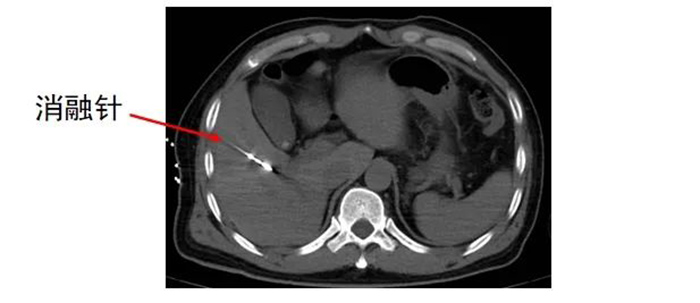

齐先生病灶临近大血管、重要脏器。厦门三院专家团队在CT引导下精准定位,经皮穿刺将微波消融针准确置入齐先生肝脏肿瘤部位,然后利用微波能量,使肿瘤组织内的水分子快速振动、摩擦产生热量,从而使局部温度迅速升高,让肿瘤细胞凝固性坏死。整个手术过程顺利,避免了严重并发症发生。

准确插入到病灶内,并避开了门静脉右支及胆,避免了出血、损伤胆囊等并发症。